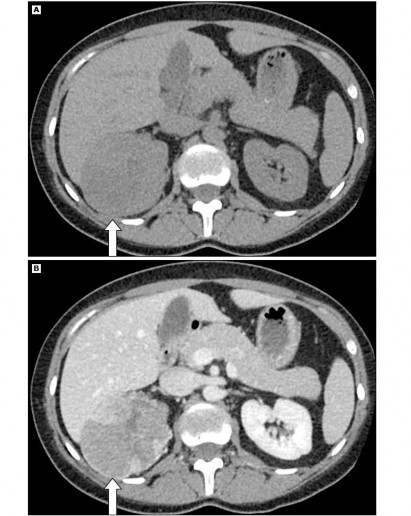

1.5.4 Đặc điểm hình ảnh của bướu ác tính

Đặc điểm hình ảnh học của bướu ác tính có một số đặc điểm gợi ý: 37,38

- Hình dạng bất thường.

- Đậm độ không đồng nhất vì có phần trung tâm giảm đậm độ do hoại tử bướu.

- Bướu có vôi hóa.

- Đường kính bướu > 4 cm.

Hình 1.7: Hình ung thư vỏ tuyến thượng thận trên phim CT scan

“Nguồn: Young W. F., Jr., 2007” 37

- Có tăng đậm độ mô ở phim CT scan không cản quang (> 20 HU).

- Đậm độ không đồng nhất ở phim CT scan có cản quang.

- Chậm thải thuốc ở phim thì thải thuốc (10 phút sau khi tiêm thuốc cản quang, lượng thuốc cản quang thải < 50%).

- Giảm đậm độ so với nhu mô gan ở phim MRI thì T1 và có tăng tín hiệu từ mạnh đến trung bình ở thì T2.

- Bằng chứng của xâm lấn mô xung quanh hoặc di căn.